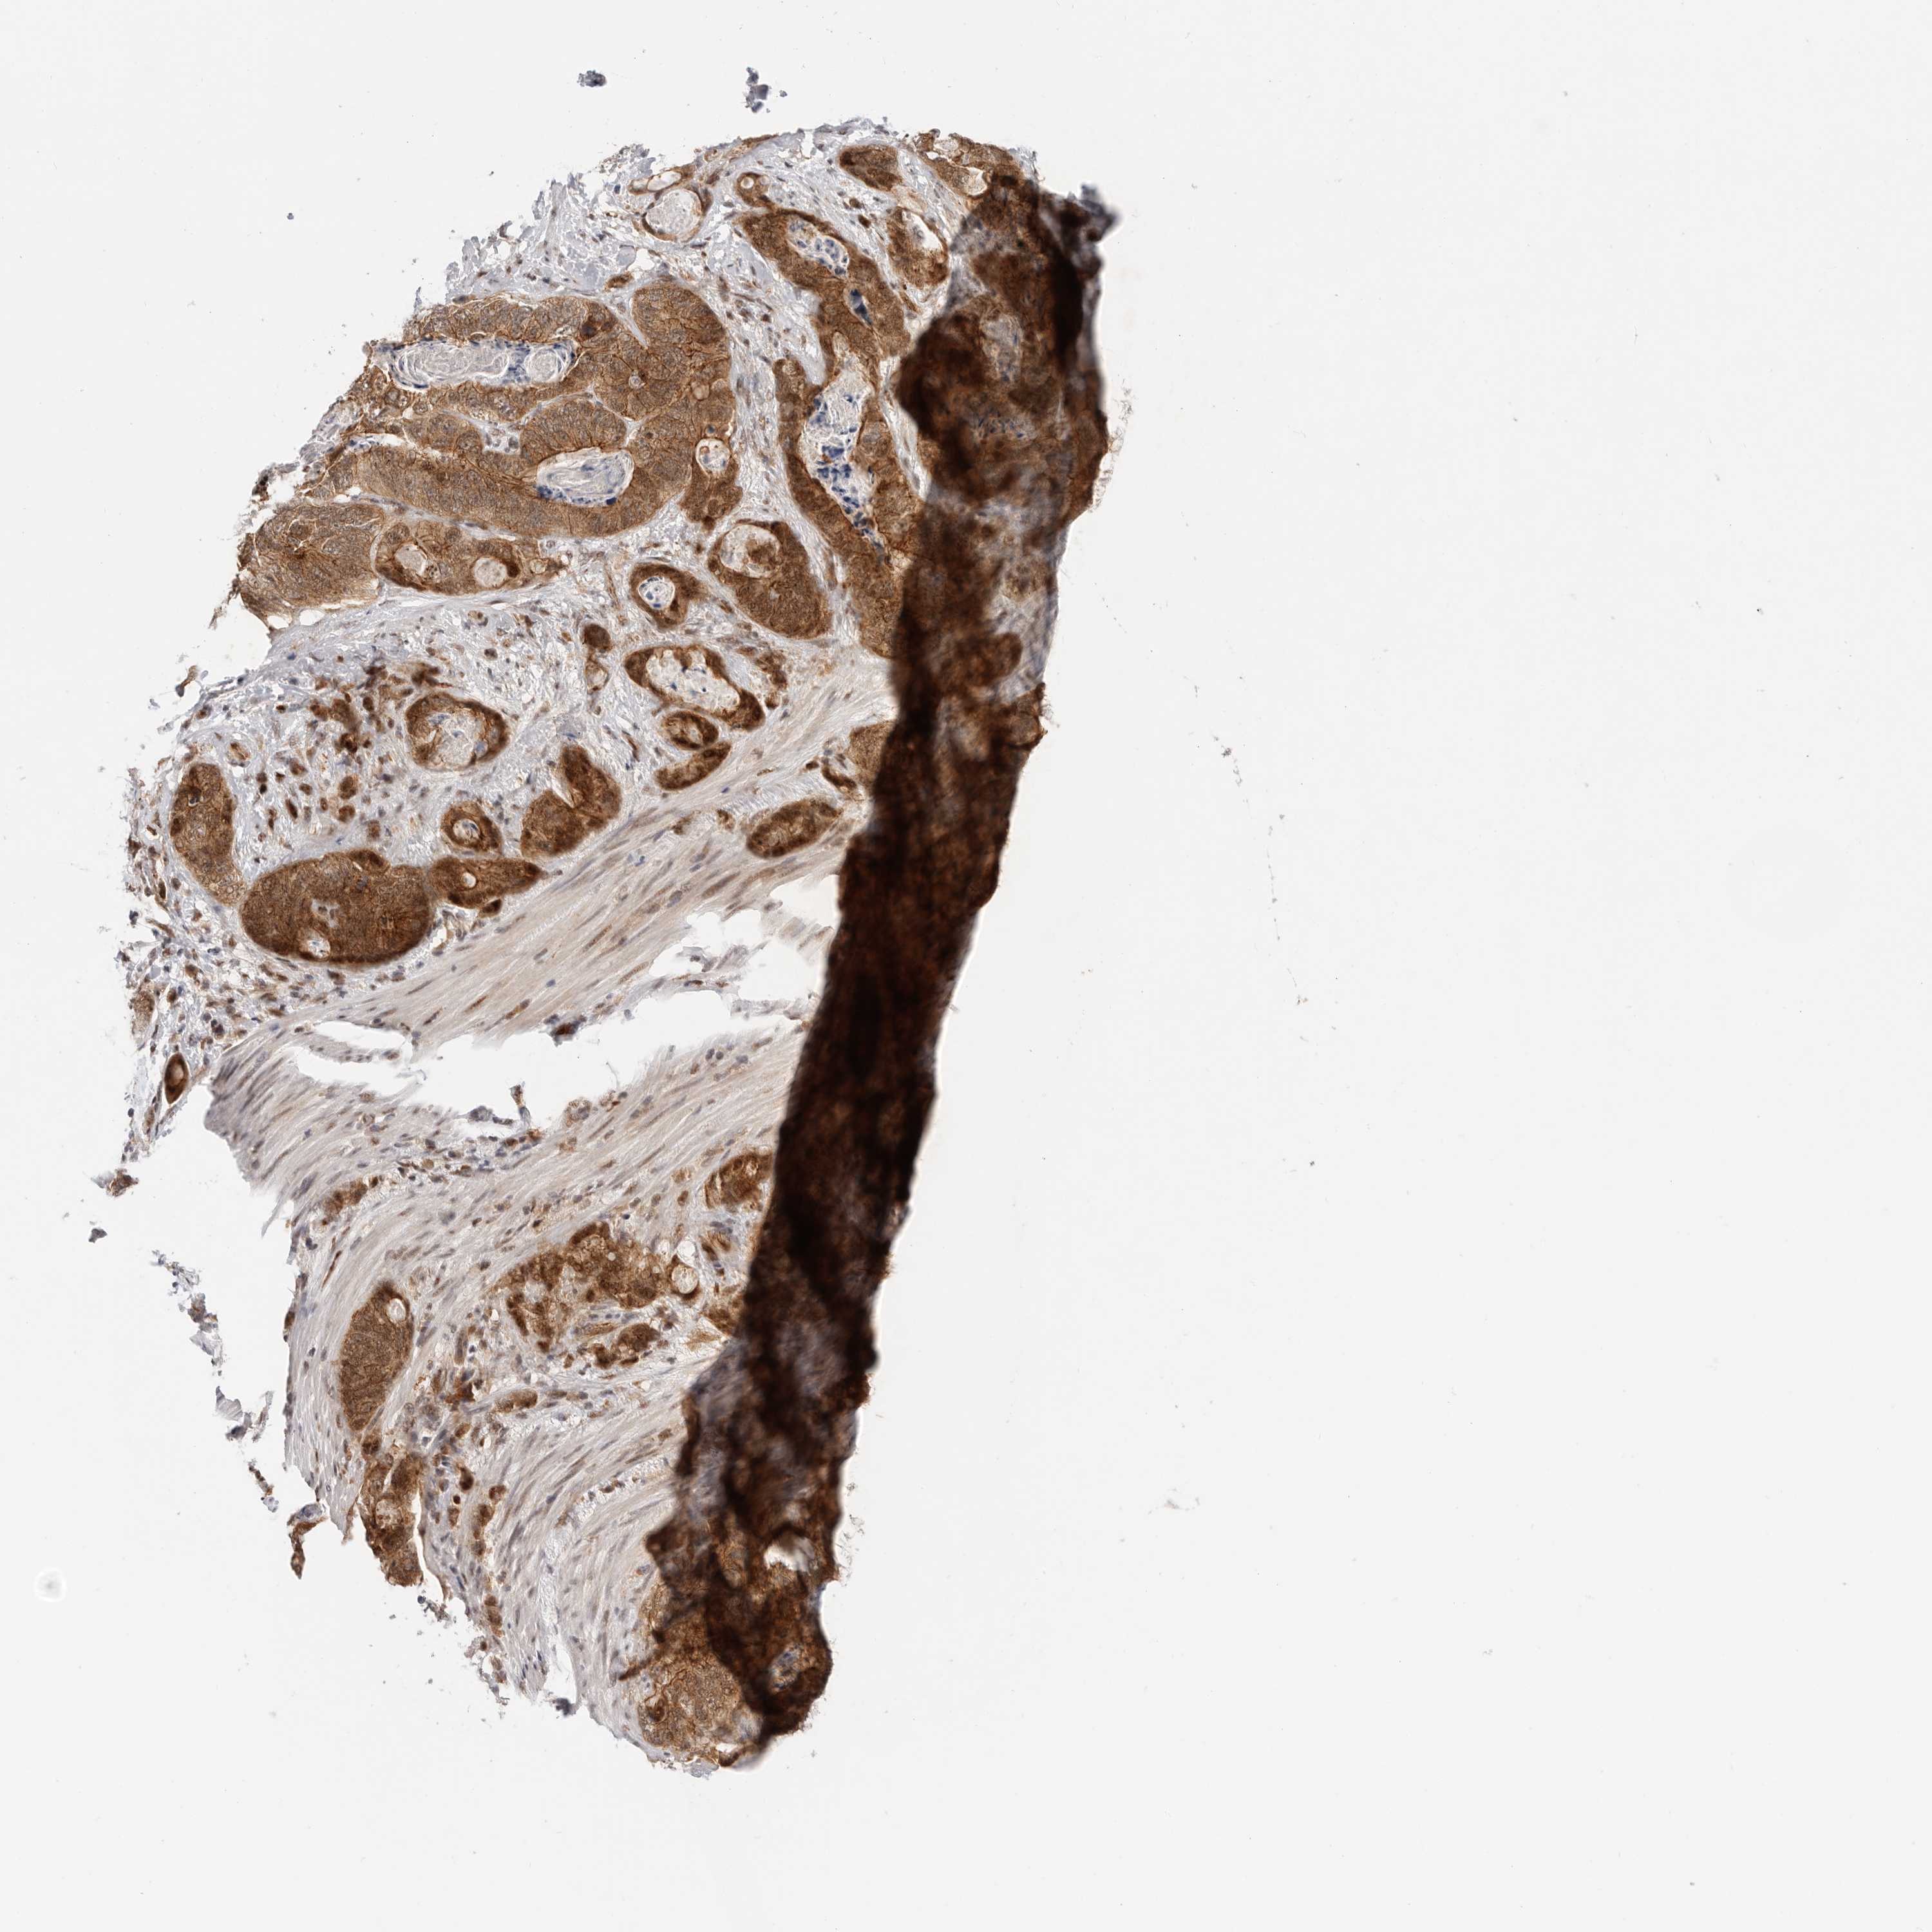

STOMACH CANCER - Protein expressioni

A mouse-over function shows sample information and annotation data. Click on an image to view it in a full screen mode. Samples can be filtered based on level of antibody staining by selecting one or several of the following categories: high, medium, low and not detected. The assay and annotation is described here.

Note that samples used for immunohistochemistry by the Human Protein Atlas do not correspond to samples in the TCGA dataset.

Antibody stainingi

Antibody staining in the annotated cell types in the current human tissue is reported as not detected, low, medium, or high, based on conventional immunohistochemistry profiling in selected tissues. This score is based on the combination of the staining intensity and fraction of stained cells.

Each image is clickable and will lead to virtual microscopy that enables deeper exploration of all samples and also displays staining intensity scores, fraction scores and subcellular localization as well as patient and tissue information for each sample.

HPA030212

HPA030213

HPA030214

HPA030215

CAB013496

Adenocarcinoma, NOS